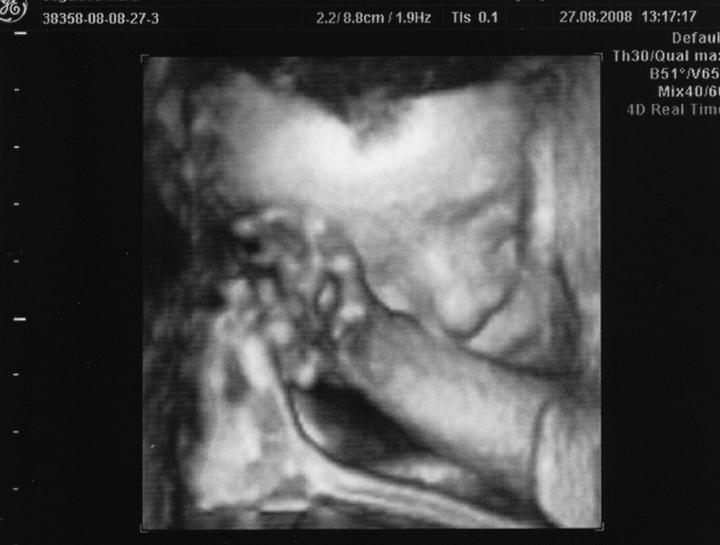

Doktor mi začátkem listopadu 2007 vysadil HA z důvodu zdravotních potíží,dávali jsme si tedy pozor a čekali,zda potíže ustoupí,ale 31.prosince 2007 mi manža řekl,že by chtěl miminko,byla jsem z jeho návrhu vykulená,ale byla to překrásná představa a tak jsem souhlasila..Od 8.ledna 2008 jsme se tedy začali snažit o miminko,začala jsem pít kontryhel a zobat Calibrum babyplan,aby mému tělu nic nechybělo 🙂 Nechávali jsme tomu volný průběh,ani jeden z nás na to nijak nepospíchal,nevím,proč jsem si říkala : Do roka se to snad povede 😀 A 29.3.2008 jsem měla pozitivní testík,sama jsem nechápala,jak brzy se to povedlo 🙂 Byla jsem neskutečně šťastná a stále jsem 🙂 Termín porodu dle MS 5.12.2008 a dle utz ve 12.tt 30.11.2008 Už od začátku jsem tušila,že čekám kluka a tak hned z první kontroly v 5.tt jsem si koupila modré bačkůrky pro štěstí,které se mnou chodili na každou kontrolu 🙂 Od 15.tt mi začalo celkem hodně tvrdnout břicho a chvilkama to bylo velice nepříjemné,na další kontrole,to jsem byla 18+4 , jsem to doktorovi řekla,ten mi pověděl,že se mu to vůbec nelíbí a tak mě poslal na utz,na utz jsem čekala 2 hodiny a můžu říct,že to byli nejhorší 2 hodiny v mém životě,tolik jsem se o miminko bála,ten strach,že něco není v pořádku byl opravdu k nevydržení..Přišla na mě řada a tak jsem tedy šla do kabinky a následně na lehátko na utz,pan doktor konstatoval,že všechno vypadá v pořádku a že se nemám bát,předepsal mi magnezium a že by to mělo pomoct,navíc koukám na ten utz a povídám panu doktorovi,to co tam vidím jsou kouličky? 😀 A on že jistě,že si myslel,že už to dávno vim,když se tak krásně ukazuje 😀 ,můj doktor mi řekl,že zřejmě porodím předčasně,což mě celkem vyvedlo z míry..Ale jsem optimisticky naladěnej človíček a tak jsem Honzíkovi vysvětlovala,že v bříšku musí ještě zůstat..Ve 20.tt jsem šla na velkej UTZ,kde mi opravdu řekli,že Honzík je zdravej a opět Honzík ukázal,že je 100% chlapeček 😀 Ve 26.tt jsme jeli na 4D utz do Liberce,tam se Honzík ukázal zas,no za celé těhu se nestalo,že by se na utz neukázal aa neroztáhl nožičky,máme malýho exibouše 😀 Ve 30.tt mě čekal další UTZ,vše v pořádku,Honzík už byl hlavičkou dolů a vážil 1600g ..Ve 35.tt mě doktor opět kvůli tvrdnutí břicha poslal už do ambulance,aby se o mě starali už tam.. Ten den jsem strávila v nemocnici 7hodin,fakt děsný !!! 2 hodiny čekání u mého doktora,ten mě tedy poslal už do nemocnice,takže jsem musela na UTZ,tam jsem čekala 2 hodiny,pak na natáčky,tam jsem čekala hodinu a pak na ambulanci a tak jsem čekala zas dvě hodiny ☹ Na UTZ ve 36.tt měl Honzík už 2600g ..